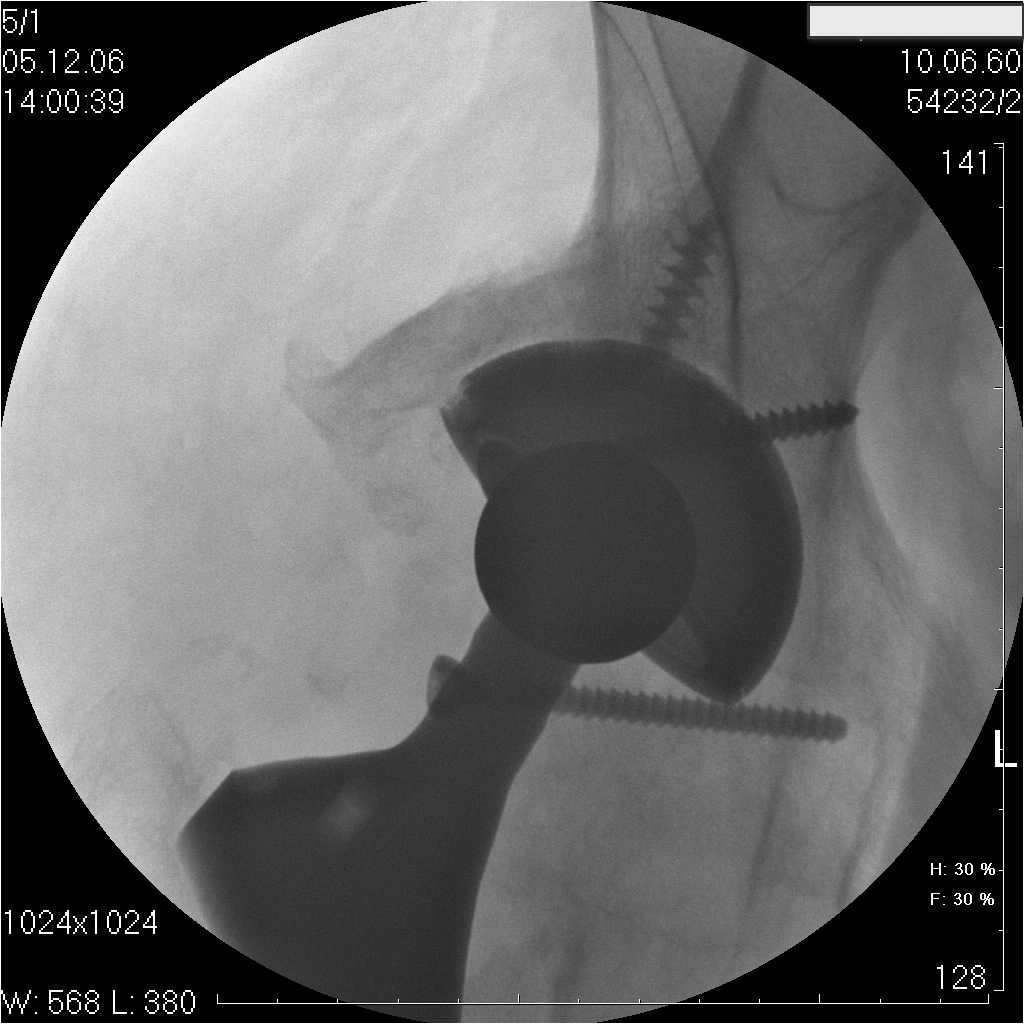

Уважаемые коллеги.В 3 Центральный Военный Клинический Госпиталь имени А. А. Вишневского, что в Красногорске, Московской области, в отделение эндопротезирования крупных суставов поступил пациент 1960 года рождения Жалобы при поступлении: на боли в области левого тазобедренного сустава (больной указывает на точку расположенная в середине условной линии между седалищным бугром и большим вертелом), усиливающиеся в начале ходьбы, при опоре на левую ногу с иррадиацией болей по наружной и наружно-задней поверхности левого бедра, левый коленный сустав; снижение объема движения в левом тазобедренном суставе, снижение опорной способности левой нижней конечности, хромоту на левую ногу, необходимость использования дополнительной опоры (костыли) при ходьбе, снижение объема двигательной активности из за болей в суставе.В анамнезе: Со слов больного, согласно медицинских документов, в 1989 году получил травму левой нижней конечности: закрытый перелом левой вертлужной впадины с центральным вывихом головки левой бедренной кости. Лечился консервативное. В процессе лечения сформировался посттравматический артроз, укорочение левой нижней конечности до 5 см. 25.04.2005 года в Подольском Окружном Госпитале Министерства Обороны выполнено: одномоменто, остеосинтез заднего края вертлужной впадины фрагментом резецированной головки бедренной кости и тотальное эндопротезирование левого тазобедренного сустава бесцементным эндопротезом "VERSIS ET" с бесцементной чашкой TRILOGY. Послеоперационный период осложнился ранним нагноением области эндопротеза, в результате санаций очага инфекции и антибиотикотерапии, активного промывного дренирования антисептиками, послеоперационная рана зажила. После операции, со слов больного, через два месяца в полном объеме стал нагружать левую нижнюю конечность. В течение полгода, после операции чувствовал себя вполне удовлетворительно. С марта 2006года стал отмечать появление болей в области тазобедренного сустава, то в области паха, то в области левой ягодицы. С августа месяца отмечает те жалобы, с которыми он сейчас к нам обратился. Температура тела, после заживления раны, нормальная. В анализах крови, лейкоциты около 7 тыс, формула нормальная, СОЭ 12 мм ч. Локально: при осмотре обеих нижних конечностей, анатомическая ось конечности не нарушена; отмечено относительное укорочение левой н\конечности на 1.5 см., гипотрофия мышц левого бедра 3 см, голени 2 см, симптом. Объем движений в тазобедренных суставах: правый~ сгибание- 60 гр, разгибание-180 гр ,отведение- 35 гр, левый~ сгибание- 110 гр , разгибание-170 гр , отведение-15 гр. Контуры других суставов н/конечностей обычные, объем движений в них не страдает. Пульсация на артериях конечностей удовлетворительная. Неврологические нарушения конечностей отсутствуют, рефлексы на обеих н/конечностях одинаковые, чувствительных нарушений нет. Осевая нагрузка на левую нижнюю конечность вызывает боль в точке расположенная в середине условной линии между седалищным бугром и большим вертелом. Отмечается пигментация и пастозность нижней трети обеих голеней и стоп, характерная для посттромботической болезни. На Цветном дуплексном сканировании сосудов нижних конечностей: Нестенозирующий атеросклероз обеих бедренных и подколенных артерий . Гемодинамически значимых препятствий кровотоку в магистральных артериях ног не выявлено. Глубокие и поверхностные вены нижних конечностей проходимы. Умеренная недостаточность клапанов подколенных вен. Данных за тромбоз глубоких вен на момент осмотра не получено.А вот что пишет наш рентгенолог: На серии рентгенограмм области левого тазобедренного сустава определяется тотальный бесцементный эндопротез. Вокруг тени чашки эндопротеза определяется ободок остеорезорбции. Кроме того, визуализируется деформированный костный винт фиксирующий консолидированный отломок вертлужной впадины, вплотную прилегающий к тени чашки эндопротеза. Заключение: Рентгеновские признаки нестабильности чашки тотального эндопротеза. Лучевая нагрузка: 6 мЗв. У нас в отделении разошлись мнения: начальник мой утверждает, после сравнения снимков, принесенных больным от августа и октября 2006года и наших рентгенснимков, что у больного нет нестабильности вертлужного компонента, и что надо назначит курс консервативной терапии: препараты кальция, миакальцик, увеличить осевую нагрузку на левую нижнюю конечность, ЛФК направления на укрепление мышц бедра, ягодиц, физиолечение. А я утверждаю, что у больного клиника нестабильности вертлужного компонента, и необходима ревизия вертлужного компонента, не исключено даже наличие инфекции под чашкой эндопротеза (не смотря на отсутствие клинических признаков инфекции). В результате проводимой консервативной терапии, боли у больного усилились. Помогите рассудить нас, мы готовы выслушать ваши мнения по этому поводу. С уважением Батал Шушания.3 ЦВКГ имени А. А. Вишневского

Ув. Коллега.Четких рентгенологических признаков нестабильности вертлужного компонента действительно нет. Здесь, кроме нестабильности, можно искать причину в поясничный отдел позвоночника(Hip-spain синдром - всё-таки 15 лет ходил с укорочением),либо сделать спиральный КТ и посмотреть, нет ли несращения в области старого перлома вертлужной впадины. Зачастую ложные суставы подвздошной, седалищной, а иногда и лонной костей являются причинами несостоятельности эндопротезов.

Уважаемый д-р Батал,

Ситуация не столь однозначная как Вам это видится. По подробно описываемой клинике с большей вероятностью речь идет о проблемах

поясничного отдела позвоночника. Есть зона остеолиза вокруг чашки, но как правило, дополнительный винт держит чашку достаточно хорошо, и даже при наличии микроподвижности, это не сопровождается столь ярким болевым синдромом. Поэтому, я бы сделал следующее: МРТ позвоночника, пункцию ТБС для исключения инфекционного процесса. Ревизию рассматривал бы как крайний вариант, учитывая выполненную костную пластику и отсутствие явных признаков нестабильности.

уважаемый коллега, Антон Вакуленко. Спасибо за четкий, расписанный по пунктам план действий. При поступлении пациента в отделение, я думал точно как вы. Но на следующий день, выполнил многопроеционное рентгенисследование, показал невропатологу, и доложил начальнику отделения о больном.После разбора пришли к следующему, да у больного действительно нестабильность вертлужного компонента, есть зона лизиса в месте костного аутотрансплантата, а в месте фиксаци чашки деротационным винтом четко выраженный контакт чашки с костной тканю. Мы пришли к выводу,что лизис костного аутотрансплантата из за осевой перегрузки на фоне незавершенного ремоделирования (вес больного 130 кг). Потому мы и приняли план вышеуказанного лечения. Провели беседу с больным, больной согласился с нами. Через 3-6 месяцев мы оценим эффективность лечения и доложу. Возможно и придется тогда идти на ревизию с заменой только вертлужного компонента а может и придется удалить весь эндопротез с установкой спейсера.. посмотрим.....

> компонента, есть зона лизиса в месте костного аутотрансплантата,

> а в месте фиксаци чашки деротационным винтом четко выраженный

> контакт чашки с костной тканю. Мы пришли к выводу,что лизис